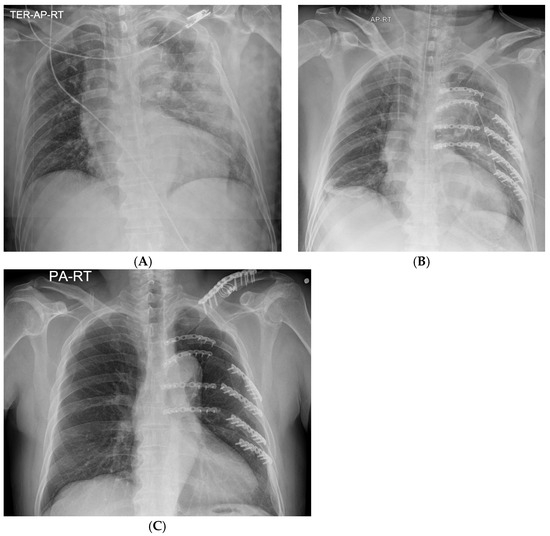

A longitudinal incision was made along the left border of the thoracic spine. Because the posteromedial fracture lines were very close to the spine and the short, fractured segments were adjacent to each other, it was impossible to secure the plate landing zones on the ribs. Therefore, the short segments were removed to decrease the risk of organ injury. With the help of a spine surgeon, rib plating (JEIL ARIX rib system, Jeil Medical, Seoul, Republic of Korea) was performed on the 4th to 7th ribs, with the medial sides of the plates anchored on the transverse processes of the thoracic spine. However, the removed segments left a space even after an effort at approximation, and the plates were placed across short floating spaces, which measured approximately 1.2 cm (Figure 3). Subsequently, a separate oblique incision was made, and the posterolateral aspects of the fractured 5th to 8th rib segments were plated for further stability and to attenuate tensile stress on the medial plates along floating portions (Figure 3, Figure 4 and Figure 5). The lung and descending aorta were inspected through a thoracotomy, and no injury was evident other than lung contusions. The pleural cavity was thoroughly irrigated, and a chest tube was placed for the management of hemopneumothorax. The following day, the patient was weaned from the mechanical ventilator and extubated. The high-flow nasal cannula was initially applied for respiratory support and was slowly tapered according to the patient’s respiratory status and ability, and the chest tube was removed on postoperative day 8. The patient required one additional general anesthesia for clavicular fracture fixation on the 10th hospital day (HD) but did not require mechanical ventilatory support post-operation. The patient was discharged from the ICU on HD 13 without clinical and pathological respiratory complications such as pneumonia and was discharged from the hospital on HD 25 after post-operative management. The patient reported minor chest pain, and a chest X-ray taken during an outpatient follow-up after discharge showed no complications (Figure 6). Figure 7 presents a timeline of the clinical hospital course of the patient.

Figure 6. Plain chest radiographs taken (A) on the admission day, (B) immediately after surgical stabilization of rib fractures, and (C) on outpatient follow-up.